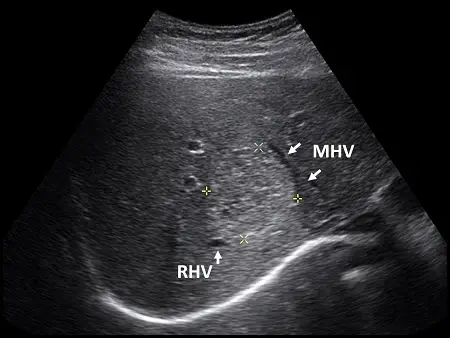

肝臟超音波橫向掃描時,發現一個高回音性病灶,介於右肝靜脈(right hepatic vein, RHV)與中肝靜脈(middle hepatic vein, MHV)之間(如下圖)。根據Couinaud classification的分類,此病灶應在肝臟的那一個節段(segment)?

本題提供的是一張肝臟的橫斷面(Transverse scan)B-mode 超音波影像。

- 探頭位置與切面:掃描位置偏向肝臟上方(superior面),因此可以觀察到肝靜脈的匯流走向下腔靜脈(IVC,位於影像深處下方)。

- 解剖標記(Landmarks):影像中清楚標示出兩條血管,分別為右肝靜脈(RHV, Right hepatic vein)與中肝靜脈(MHV, Middle hepatic vein)。

- 病灶特徵:在 RHV 與 MHV 之間,可見一個邊界清晰的「高回音性(Hyperechoic)病灶」(游標十字記號所標示處),其回音度明顯高於周圍正常的肝實質。此類高回音性腫塊在臨床超音波中最常見的良性病灶為肝血管瘤(Hemangioma)。

- (A) 8(VIII):正確。中肝靜脈(MHV)分隔了左肝葉與右肝葉,右肝靜脈(RHV)則將右肝葉分為前段與後段。介於 MHV 與 RHV 之間的區域為「右肝前段(Right anterior sector)」。又因為此切面能看到肝靜脈匯流入下腔靜脈,屬於肝臟的上半部(Superior portions),因此該區域為第 8 節段(Segment VIII)。

- LHV 的左側/外側:左外葉上段 (Segment II) 題目影像中的高回音病灶明確坐落於中肝靜脈 (MHV) 與右肝靜脈 (RHV) 之間,因此該病灶位於第 8 節段(Segment VIII)。故本題正確答案為 (A)。